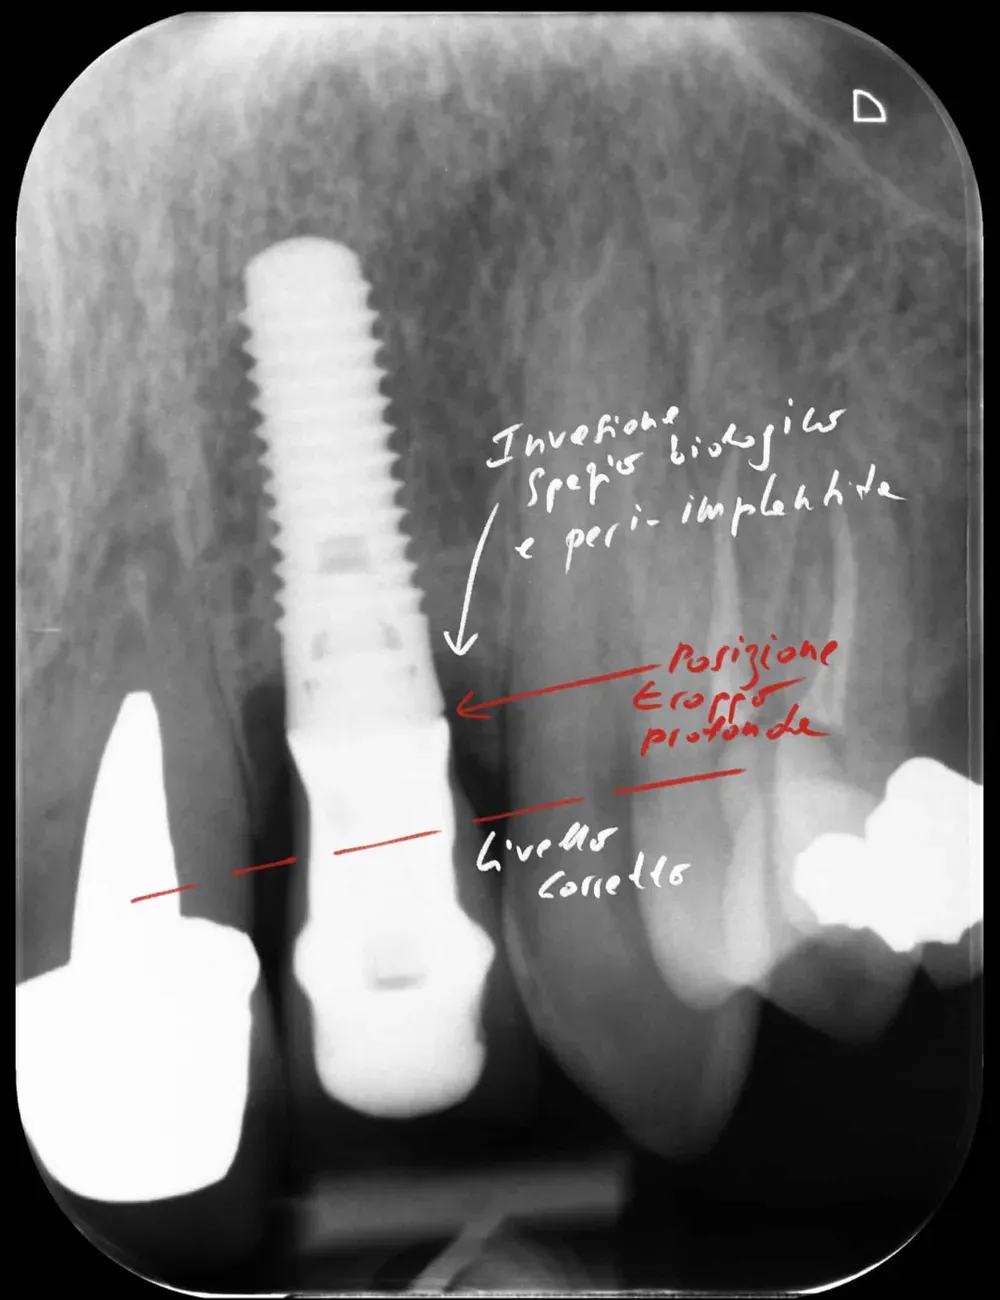

Il tissue level posizionato male

Gli impianti tissue level nascono con un obiettivo preciso: spostare l’interfaccia protesica lontano dall’osso, a livello dei tessuti molli. Il microgap — quella zona di colonizzazione batterica inevitabile tra impianto e componente protesica, caratteristico soprattutto di alcuni tipi di connessione — viene così allontanato dalla cresta ossea.

Utilizzarli come se fossero bone level, o peggio ancora affondarli più in profondità, è un errore biologico grave (ne ho parlato anche in questo articolo sulle conseguenze biomeccaniche del malposizionamento). Quando il microgap si trova troppo vicino alla cresta, si innesca un riassorbimento osseo progressivo. Di fatto, in tali casi, parliamo di una vera e propria invasione dello “spazio biologico”, concetto prezioso in odontoiatria. La peri-implantite, in questi casi, non è un rischio: è una conseguenza prevedibile ed è dietro l’angolo .

Gli impianti transmucosi devono essere posizionati transmucosi, soprattutto se hanno connessioni non particolarmente “sigillanti”. Usati in tal guisa, sono perfetti. Le immagini che seguono dimostrano che i transmucosi, se posizionati al giusto livello verticale, causano ZERO riassorbimento della cresta ossea.

Non sono fatti per invadere lo spazio biologico. Devono starne fuori.